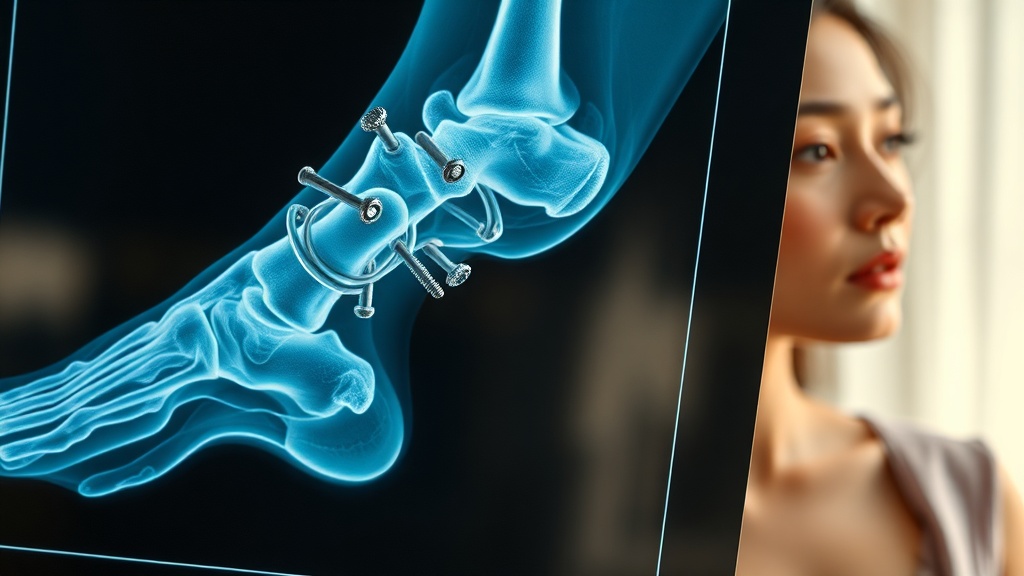

次に投稿されたのは、彼女の脚のレントゲン写真でした。そこには、折れた骨を固定するために、数え切れないほどの鉄心(ボルトやプレート)がびっしりと埋め込まれた衝撃的な光景が写っていたのです。

オム・ジウォンさんは写真と共に「骨がくっつくにはまだ早い時期ですが……一生懸命リハビリ中です」と綴り、見た目以上に深刻な怪我であったことを明かしました。かつて「骨がバラバラになった」と表現したこともあるほどの大怪我。現在は日常生活を取り戻すため、懸命に治療に励んでいる最中だといいます。